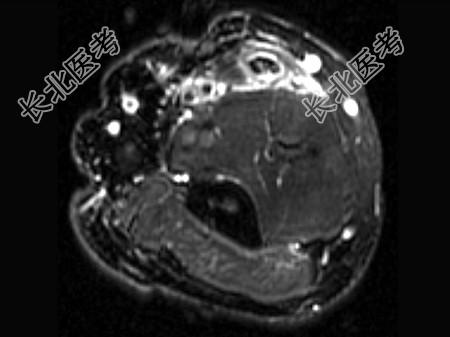

- 单项选择题女,44岁, 有外伤史,上臂远端疼痛, 结合图像,最可能的诊断是 ( )

D、肱二头肌腱远侧局部裂伤